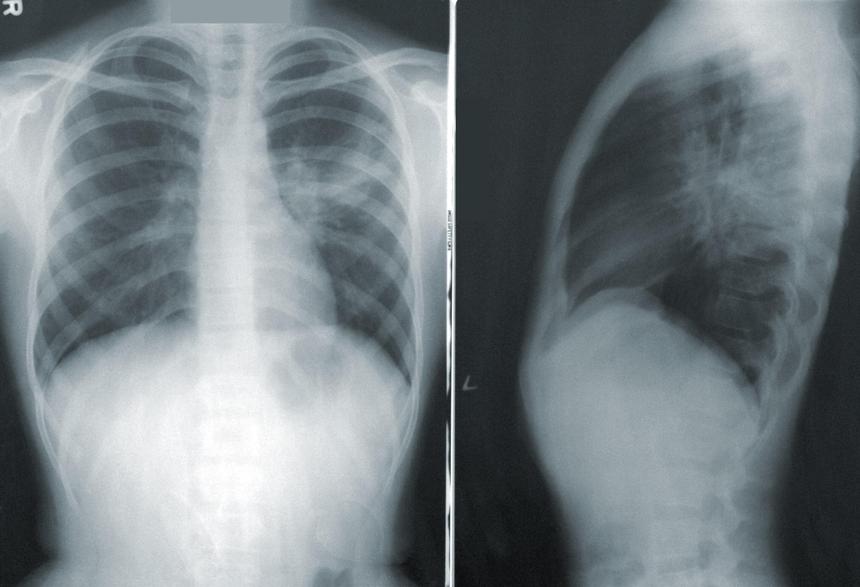

Новое исследование показало, что образование и доход связаны с тем, на какой стадии у пациента будет обнаружен рак лёгких. От этого напрямую зависит выживаемость.

Учёные рассказали, что пациенты с более низким уровнем дохода и образования, а также те, кто живёт в регионах с более ограниченными социально-экономическими ресурсами, непропорционально плохо выживают при раке лёгких. Расовые/этнические меньшинства в США также сталкиваются с более высокими показателями смертности от рака лёгких.

Исследователи проанализировали данные за 2004-2016 годы о пациентах в возрасте 18-89 лет, у которых была диагностирована любая стадия рака лёгких. Исследователи также собрали информацию об уровне образования и дохода в районах, в которых проживали пациенты.

У людей, живущих в районах с самым низким уровнем образования и в районах с самым низким доходом, шансы обнаружить рак лёгких только на поздней стадии были на 12% и 13% соответственно выше. «Наши результаты подтверждают, что бедность является основной причиной неблагоприятных исходов рака лёгких», — отметили учёные.